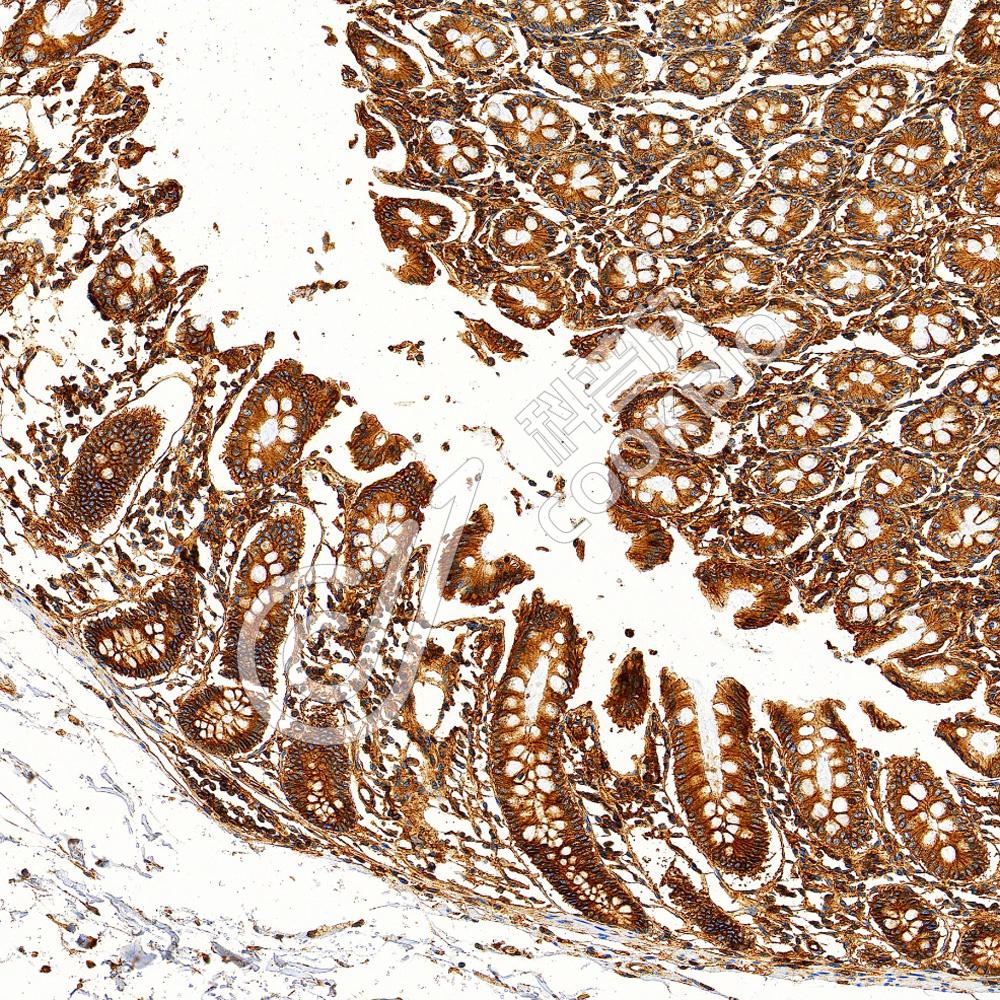

IHC检测Myeloperoxidase蛋白(货号 K2360048).

样品: 小鼠lps(24h)诱导肝脏炎症模型, 4%多聚甲醛 (货号KSG1101) 固定12-24小时.

抗原修复: 柠檬酸抗原修复液(干粉, pH 6.0) (KSG1201), 高压锅均匀喷气计时2分钟.

—抗: 1: 1000稀释, 4℃ 孵育过夜.

二抗: S-vision免疫组化多聚二抗(山羊抗小鼠), 即用型(货号KB3903), 室温孵育20分钟.